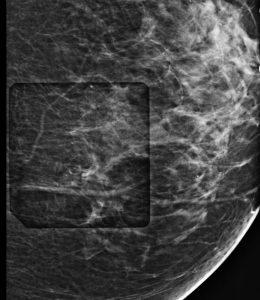

Master the skills for performing Stereotactic and Tomosynthesis-guided breast biopsies. This course covers indications, procedures, and guidelines for both methods, including equipment, patient positioning, and techniques. Learn to identify and address challenges, optimize biopsy accuracy, and ensure patient safety and care for diagnostic efficiency.